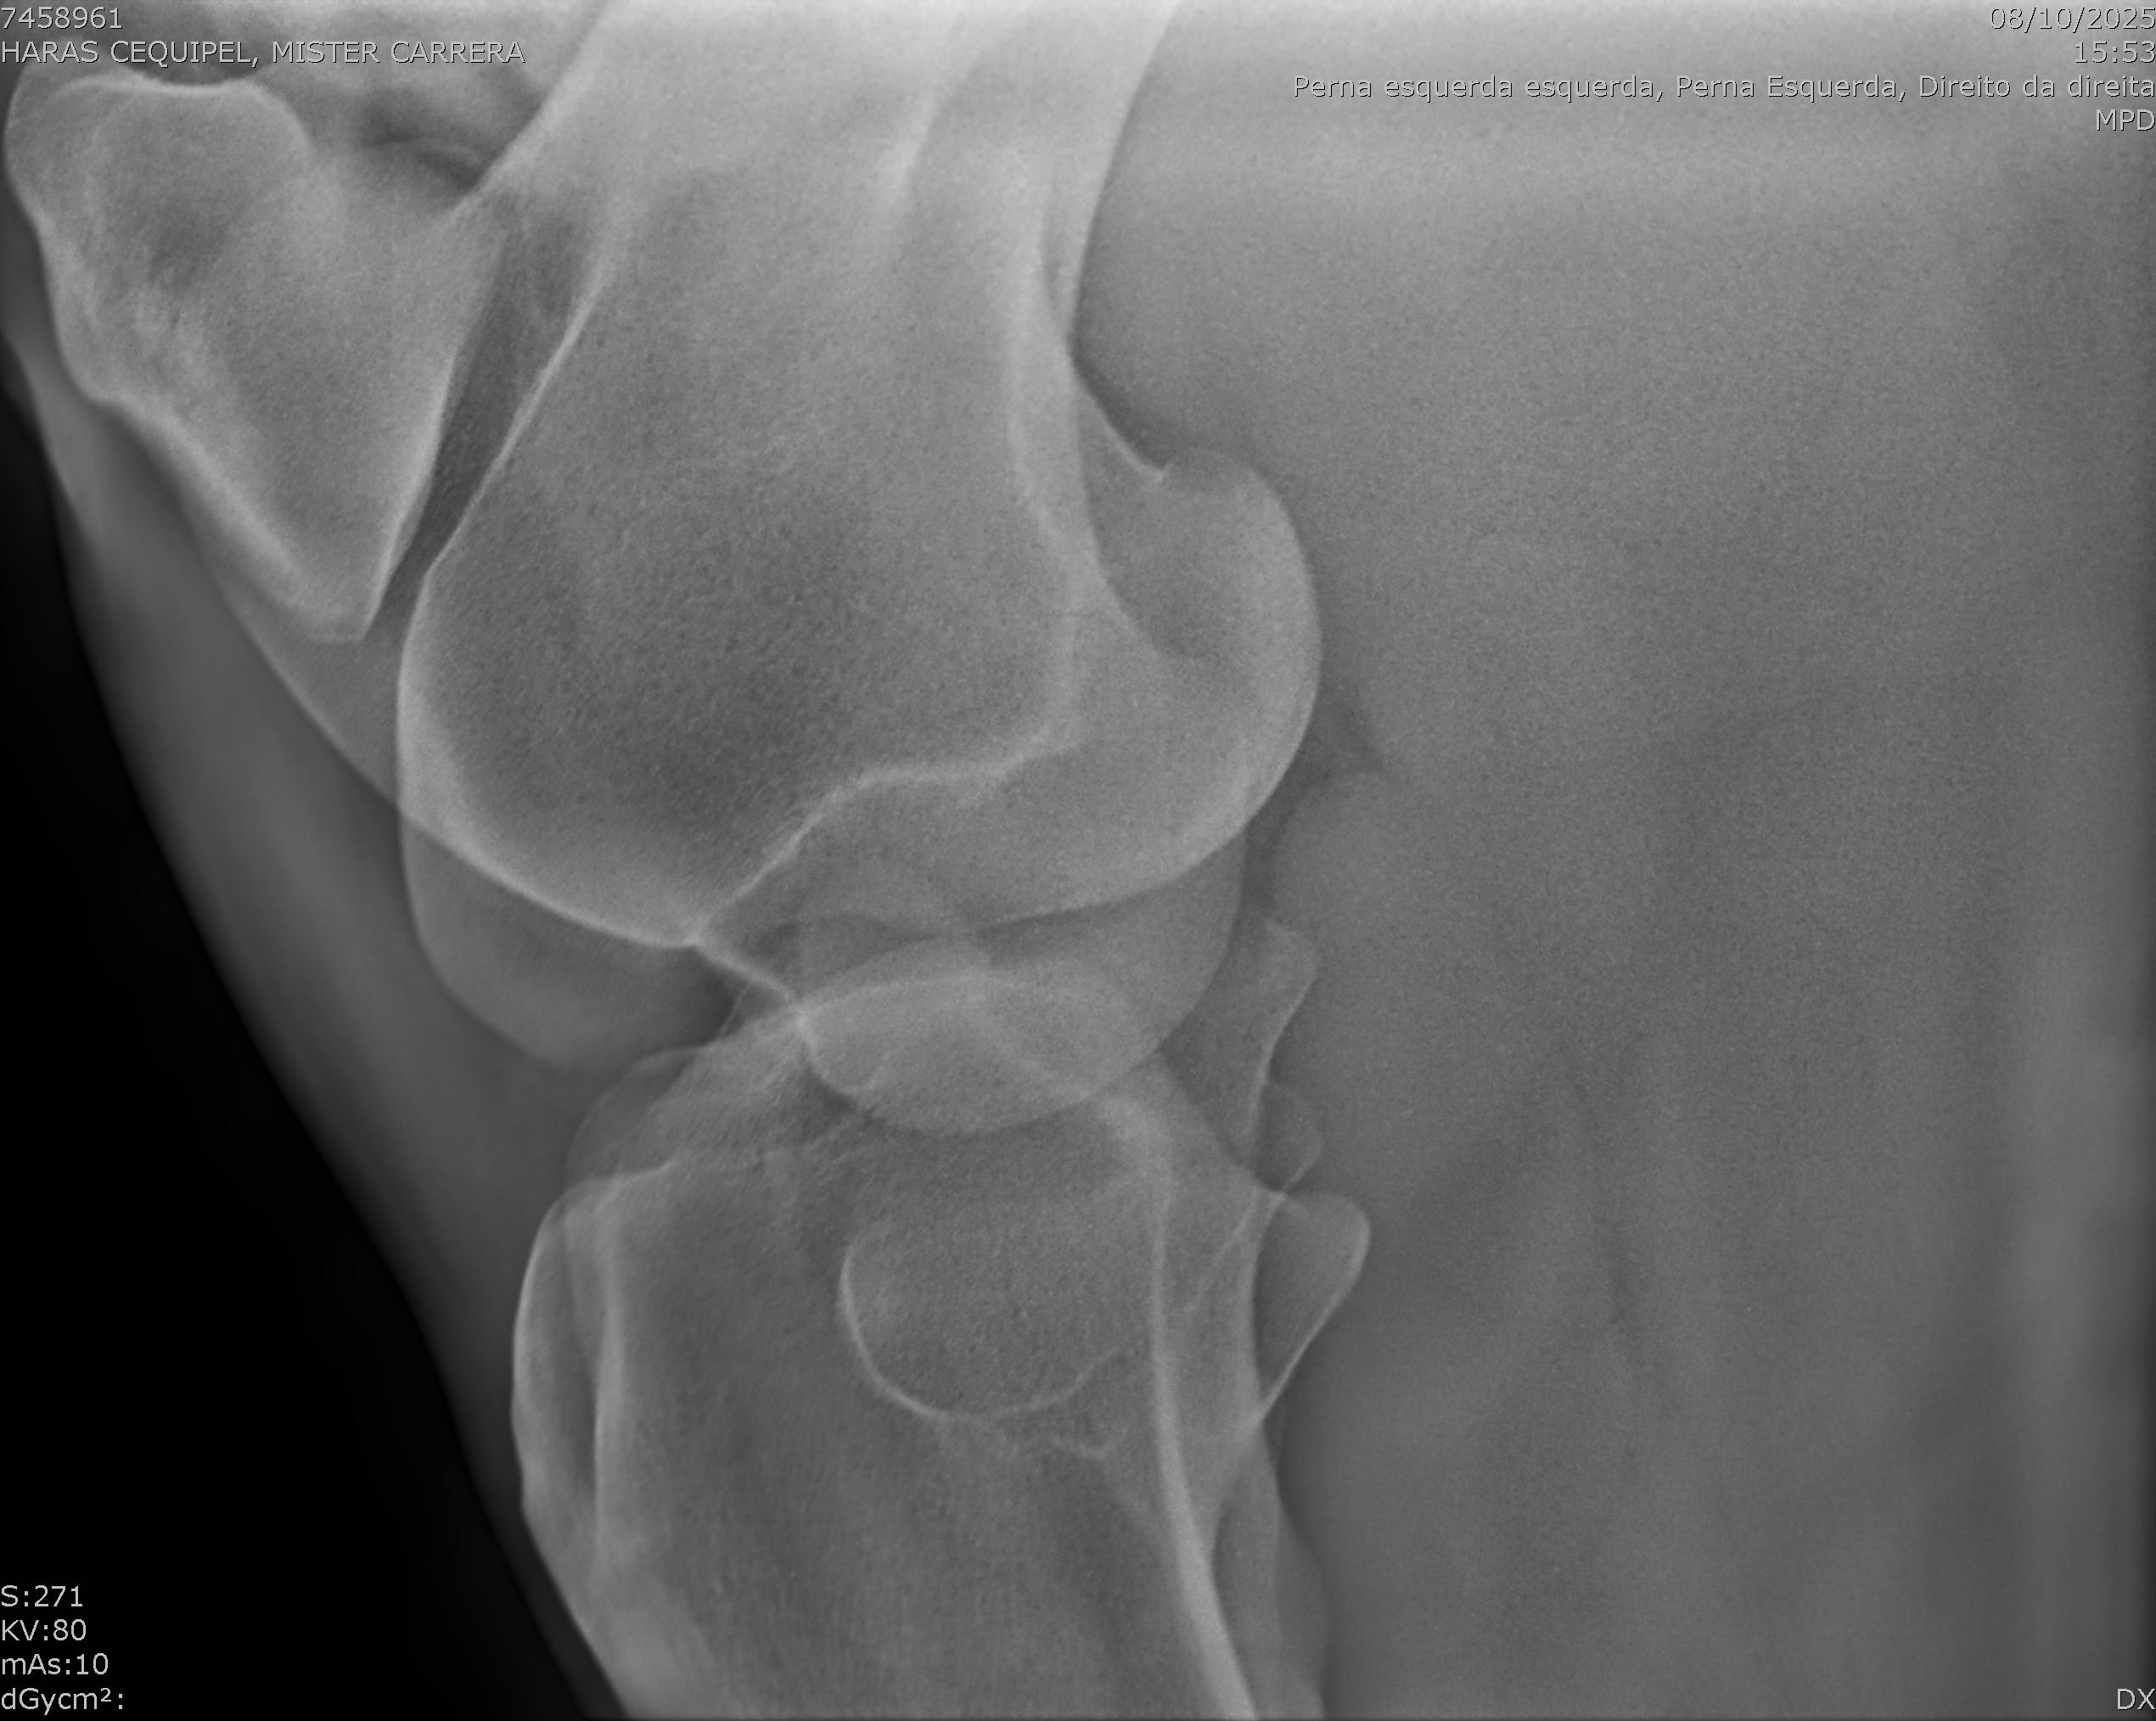

:: RAIOS-X DO LOTE